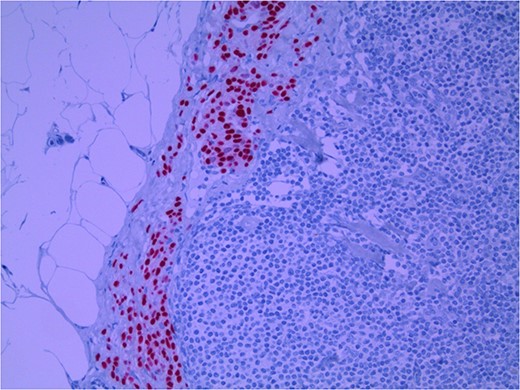

Lymph node specimens were sent for haematoxylin and eosin (H&E) staining (Fig. 3) and IHC analysis. The sections showed mild reactive changes and benign intracapsular nevoid rests. IHC analysis showed that these cells were negative for HMB-45 (Fig. 4) and were positive for both Sox10 and p16 (Figs 5 and 6). Consensus at the Multidisciplinary Team Meeting was that the appearance was in keeping with benign naevoid rests as opposed to melanoma deposits, given the location of the cells, morphology and immunohistochemistry. Surveillance was recommended.

Lymph node with IHC using Sox 10 stain, staining melanocytic cells (benign or malignant) in subcapsular region; × 200 magnification.